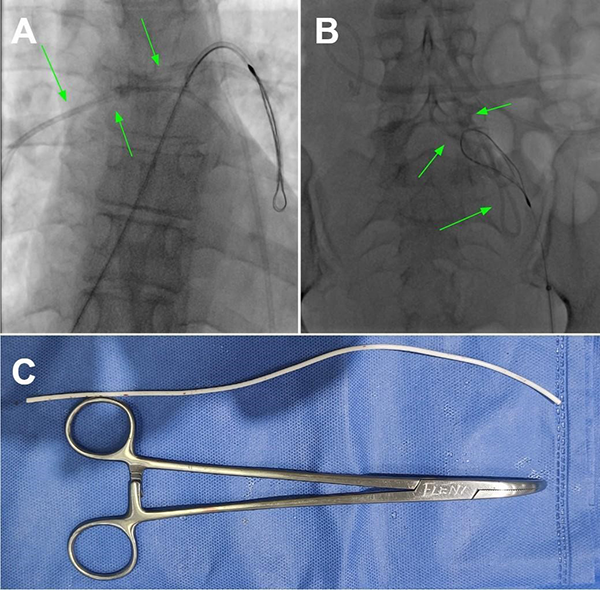

Tras 2 meses, la paciente volvió a consultar en guardia por náuseas, cefalea bifrontal con irradiación holocraneana de intensidad moderada y vómitos. Al examen físico se constató limitación de la mirada superior y colección líquida sobre herida craneal de derivación. Se realizó TC de cerebro con evidencia de ventriculomegalia y desconexión de catéter distal a la válvula (Figura 1). El estudio radiográfico reveló migración caudal del segmento distal del catéter al corazón (Figura 2). El segmento migrado fue rescatado mediante un abordaje endovascular transfemoral, en el cual se enroscó el catéter migrado con un catéter pigtail y se lo desplazó hasta la vena ilíaca primitiva izquierda para luego ser capturado a nivel ilíaco con un lazo trilobulado (Figura 3).

Figura 3. A. y B. Imágenes radioscópicas del procedimiento endovascular efectuado en el cuál se recupera y exterioriza el catéter distal migrado. C. Fotografía del catéter una vez retirado.